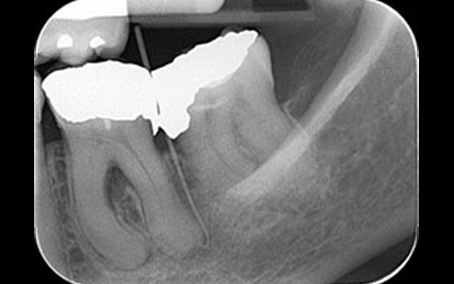

Pre Op Radiograph

Post Op Radiograph